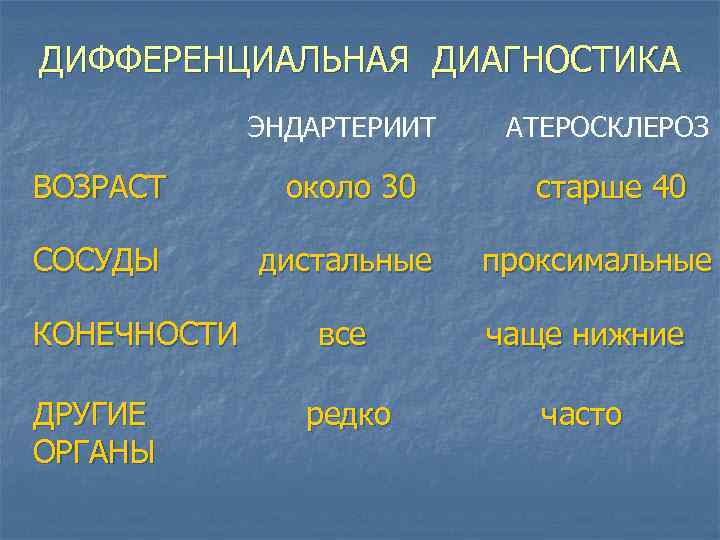

ДИФФЕРЕНЦИАЛЬНАЯ ДИАГНОСТИКА ЭНДАРТЕРИИТ ВОЗРАСТ около 30 СОСУДЫ дистальные КОНЕЧНОСТИ ДРУГИЕ ОРГАНЫ АТЕРОСКЛЕРОЗ старше 40 проксимальные все чаще нижние редко часто